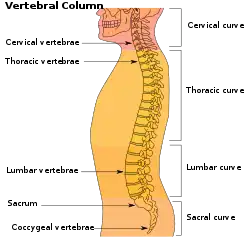

The lumbar (or lower back) region is the area between the lower ribs and gluteal fold which includes five lumbar vertebrae (L1–L5) and the sacrum. In between these vertebrae are fibrocartilaginous discs, which act as cushions, preventing the vertebrae from rubbing together while at the same time protecting the spinal cord. Nerves come from and go to the spinal cord through specific openings between the vertebrae, receiving sensory input and sending messages to muscles. Stability of the spine is provided by the ligaments and muscles of the back and abdomen. Small joints called facet joints limit and direct the motion of the spine.[34]